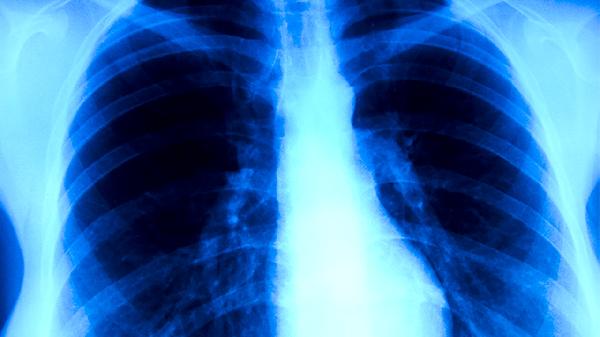

肺炎患者可在医生指导下使用金银花、鱼腥草、板蓝根、黄芩、连翘等中草药辅助治疗。肺炎多由细菌、病毒等病原体感染引起,临床表现为发热、咳嗽、咳痰等症状,需结合西医抗感染治疗。